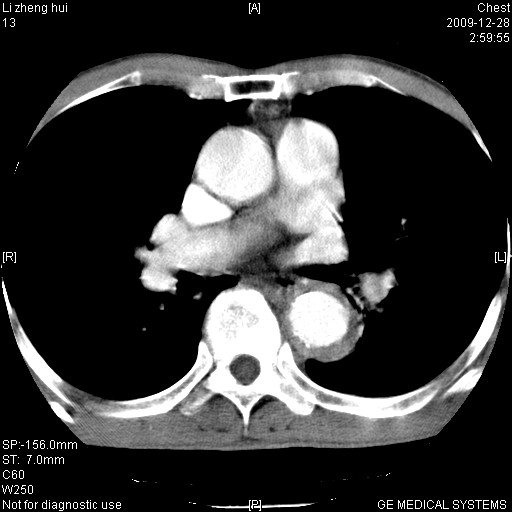

标题: CT23859:胸主动脉瘤

男  79岁 胸部痛急诊入院,晚上做的增强

考虑主动脉瘤?(增粗、钙化、壁血栓?)

支持降主动脉夹层

支持降主动脉瘤,不考虑夹层

动脉瘤伴附壁血栓

主动脉壁内血肿?

1)考虑胸主动脉壁间血肿或夹层动脉瘤。2)多发性肝囊肿。

1)考虑胸主动脉附壁血栓或夹层动脉瘤。2)多发性肝囊肿。